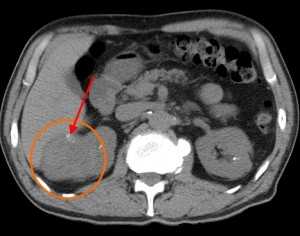

В артериальную фазу становится хорошо различимой неоднородная структура опухоли, т. к. солидная ее часть (активная часть опухоли, хорошо снабженная сосудами) интенсивно усиливается и становится гиперденсной, а кистозная часть никак не накапливает контраст и остается той же плотности, что и в нативную фазу. В венозную фазу опухоль задерживает контраст интенсивнее, чем почечная паренхима, вследствие чего выглядит более гиперденсной, более плотной. В отсроченную фазу уже через 10 минут после начала введения типичный рак не накапливает контраст, зато хорошо становится видна чашечно-лоханочная система - появляется возможность оценить ее контуры на предмет прорастания новообразования внутрь.